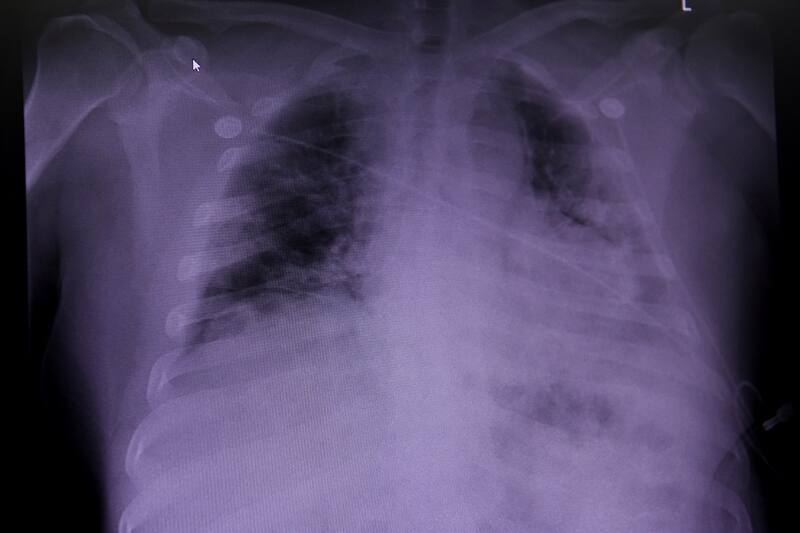

Un estudio de la Facultad de Medicina de la Universidad de Washington en St. Louis ha descubierto una forma sencilla de predecir qué pacientes hospitalizados sufrirán complicaciones o la muerte. Mediante un análisis rápido de sangre que mide el ADN mitocondrial, los investigadores pudieron detectar pacientes que luego enfrentarían los casos Covid más graves en un grupo de 100 personas hospitalizadas.

El equipo investigador encontró que los niveles de ADN mitocondrial aumentaron diez veces más en pacientes con coronavirus que desarrollaron una disfunción pulmonar severa o que murieron más tarde. Estas personas tenían “casi seis veces más probabilidades de ser intubados, tres veces más probabilidades de ser admitidos en la Unidad de Cuidados Intensivos (UCI), y casi el doble de probabilidades de morir en comparación con aquellos pacientes que presentaban niveles más bajos”, afirmó el estudio.